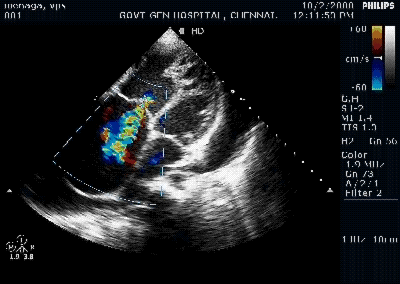

The following illustration (From Ref 2 ) summarizes all RV functional parameter in a succinct fashion. Fellows must be familiar with at-least half of them.( RIMP is less practical and error prone can be ignored)